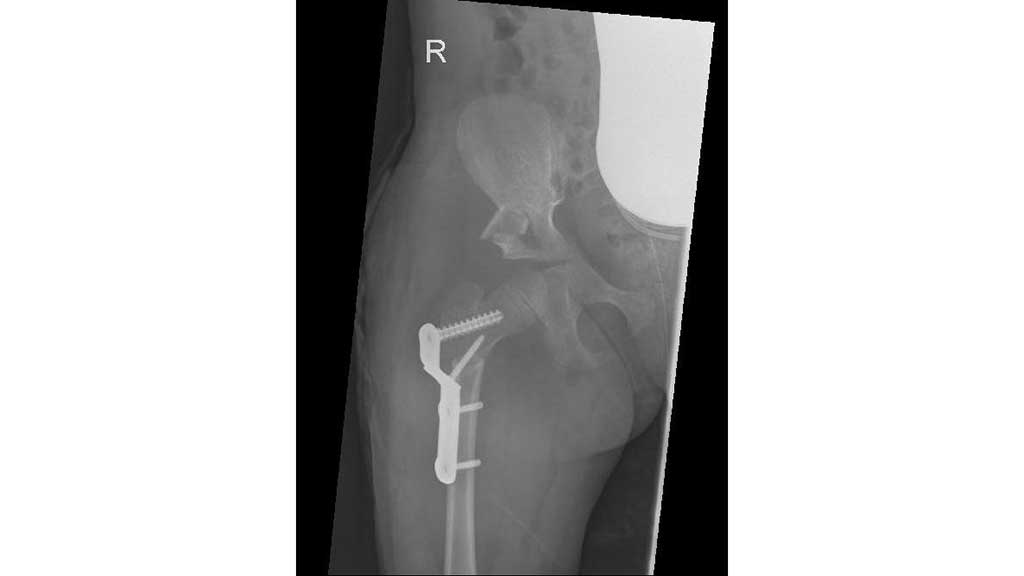

Im Frühjahr 2012 erfolgte dann die umfangreiche Hüftoperation: Adduktorentenotomie beidseits, Psoas-Tenotomie rechts, offene Reposition und DVO und Pfannendachplastik nach Dega mit Surfixplatte rechts (Abb. 8).